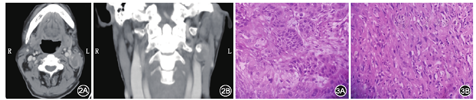

患者男,65岁,因"咽痛2个月"于2018年2月24日就诊于青岛市市立医院耳鼻咽喉头颈外科。入院检查见患者消瘦,左侧扁桃体表面为黄白色、形态不规则肿物,外生性生长,范围超越中线,但其基底未侵犯软腭及悬雍垂,软腭活动正常(图1);向下波及部分舌根组织,但下咽侧壁及劈裂、声门未侵犯,声带活动正常。左侧颌下区可触及一个大小约3 cm×2 cm×2 cm的质硬淋巴结,位置固定,无压痛。患者既往有糖尿病史、胃结石及胃镜下取石术史。增强CT提示左侧Ⅱ区淋巴结转移可能,且转移淋巴结内可见明显钙化影(图2)。行扁桃体肿物活检提示:左侧扁桃体鳞状细胞癌(图3)。入院诊断为:左侧扁桃体鳞状细胞癌伴淋巴结转移;糖尿病;胃结石史。术前胃镜检查排除食道及胃部肿瘤,排除肺、脑、骨等器官病变,控制血糖<8 mmol/L后于2018年2月28日在全麻下行左侧扁桃体癌根治术+舌根部分切除术+Ⅰa区及左侧Ⅰb区、左侧Ⅱ、Ⅲ、Ⅳ区淋巴清扫术+颌下腺切除术。术中见左侧Ⅱ区淋巴结与颈內静脉粘连明显。冰冻切缘阴性,舌根部创面对位缝合。手术顺利。术后予以对症支持治疗,创面逐渐愈合。术后石蜡病理报告:①扁桃体中分化鳞状细胞癌,癌组织侵及横纹肌,脉管内可见瘤栓;②颌下腺未累积;③(Ⅱ、Ⅲ、Ⅳ区)淋巴结(1/21)见恶性瘤细胞转移,结合免疫组化,肉瘤可能性大;免疫组化:Ki-67(约70%+)、p63(+)、p53(突变型)CK5/6(+)、CD34(瘤栓-)、D2-40(瘤栓+)、p16(-)、p40(+)、CK(-)、Vim(+)。因病理结果提示原发灶扁桃体肿瘤为中分化鳞状细胞癌(简称鳞癌)而转移淋巴结提示肉瘤,两者性质不统一,再次行免疫组化以明确肉瘤性质及来源。同时完善检查以排除其他组织与器官肉瘤,腹膜后超声未见明显异常。第二次免疫组化结果,提示1个(1/21)淋巴结内见癌组织转移,可见恶性瘤细胞呈梭形,弥漫分布,核分裂象多见,可见钙盐沉着及骨样基质,考虑鳞癌转移伴肉瘤样分化,原免疫组化另增加S-100(-)、Desmin(-)、SMA(-)、CD35(-)、CD21(-)、actin(-)、CD34(-)、CD68(+)、β-catenin(-)。该患者术后于第5周开始进行放化疗(60 Gy+TP方案)联合治疗,5个半月后因肺转移及并发症死亡。